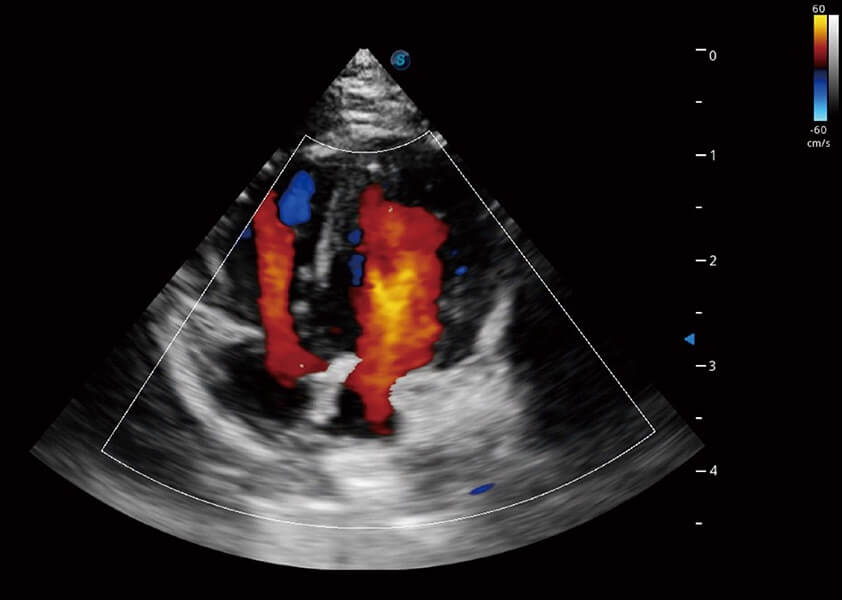

ProPet 60 作为一款高端台式动物超声设备,为动物医生的日常诊断提供了一系列贴合动物临床需求、解决临床实际问题的高级成像功能。凭借全系列高清探头,满足医生对腹部、心脏、生殖、浅表、肌骨等成像的所有需求,切实帮助您提升检查效率,提高诊断信心。

动物是人类最亲密的朋友和最值得信赖的伙伴。亚星官网也一直致力于探索动物专用的超声影像解决方案。 全新推出的ProPet系列,是亚星官网在动物超声影像智能化、专业化、精准化的一次跨越式革新。动物不能用言语来表述自己的不适,通过超声影像,ProPet系列搭建了动物医生与不同物种沟通的“桥梁”,为动物医生注入了“治愈之力”。